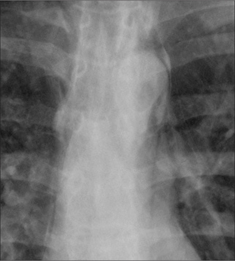

image

Figure 29.4 Acute asthma. Pleuritic chest pain. Extensive mediastinal emphysema. The process causing the emphysema is explained on pp. 123–124.